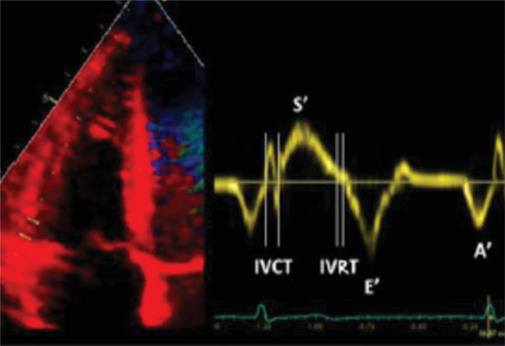

Results: Right ventricular basal diameter was significantly higher in groups chronic kidney disease (CKD) V and HD than control. Right ventricle tricuspid annular plane systolic excursion (RV TAPSE) and RV tissue Doppler imaging(S') were significantly lower in CKD Group V than HD and control group. Pulmonary HTN is present in 22% of renal patients with significantly higher prevalence in HD group. There was a positive correlation between the estimated glomerular filtration rate (eGFR) and RV TAPSE and between eGFR and RV (S') of CKD IV and CKD V groups. There was a negative correlation between RV TAPSE and pulmonary arterial systolic pressure by echocardiogram of the studied groups. There was a positive correlation between RV TAPSE and RV (S') of the studied groups.